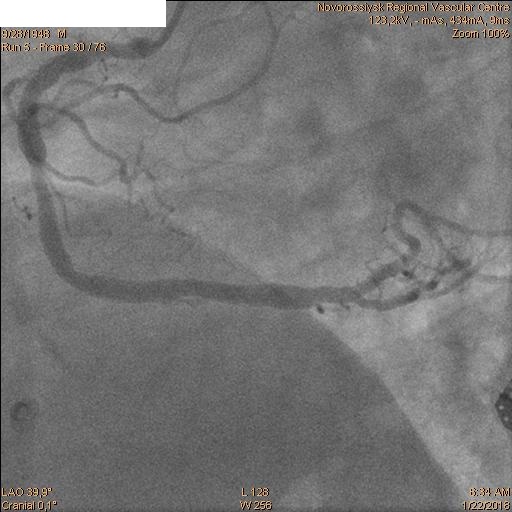

Затем последовательно перепроведены коронарные проводники в дистальные сегмента ПНА и ОА. Баллоном 2.5х20 мм выполнена предилатация ячеек стента. Далее выполнено стентирование ствола ЛКА с переходом на проксимальный сегмент ОА стентом 4.0х28 мм. Затем баллонами 2.5х20 мм и 2.5х15 мм выполнена «kissing» дилатация ствола ЛКА, устья ПНА и устья ОА с великолепным ангиографическим результатом.

Пациент переведен в ПИТ отделения неотложной кардиологии. ЭКГ после операции.

Отличный результат! Был выполнен Cullotte?

Спасибо! Да.